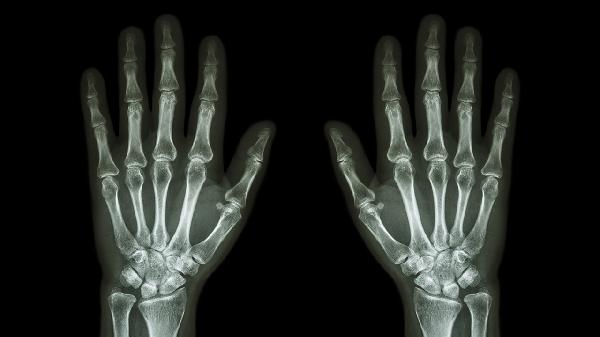

外力挫伤手指关节肿痛怎么办

外力挫伤手指关节肿痛可通过休息制动、冷敷处理、药物治疗、热敷缓解、康复训练等方式治疗。外力挫伤通常由撞击、挤压、扭伤、骨折、韧带损伤等原因引起。